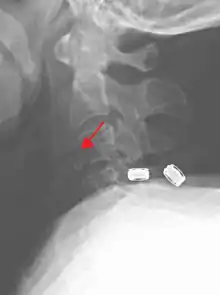

On CT scan or X-ray, a cervical fracture may be directly visualized. In addition, indirect signs of injury by the vertebral column are incongruities of the vertebral lines,[6] and/or increased thickness of the prevertebral space:[7]

X-ray of normal congruous vertebral lines